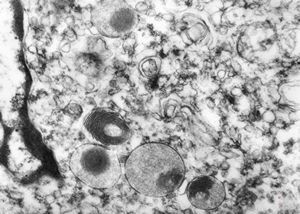

myelinoid inclusion in an unclassified tumor - peroxisome?

myelinoid inclusion in an unclassified tumor - peroxisomes?